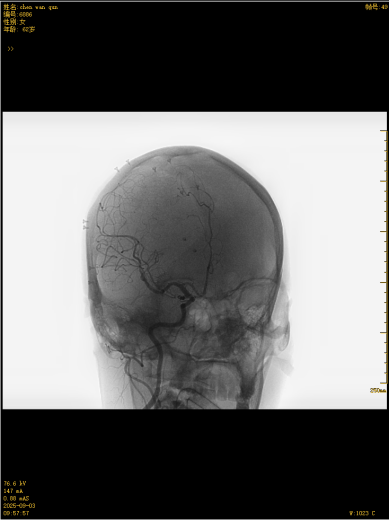

这款国产创新技术的优势不止于疗效:通体显影设计让支架定位精准到毫米级;超弹性材质与优化编织工艺实现极致贴壁,兼顾支撑力与柔顺性,适配复杂迂曲脑血管;操作更轻巧、创伤更小,仅需大腿根部米粒大小切口即可完成手术,可实现患者术后可快速康复。本次手术中,团队在DSA引导下精准释放支架,全程耗时短、出血少,术后造影显示,动脉瘤内血流即刻变得迟缓,载瘤动脉通畅,重要分支血管保护完好。患者术后恢复良好,未出现任何神经功能障碍,术后不久即快速康复出院,重获健康,恢复正常生活工作。